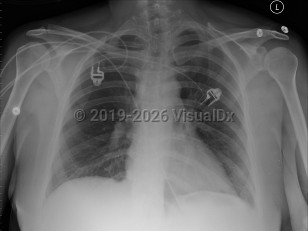

Pulmonary embolism

A PE is a blood clot that typically originates from thrombi in the deep venous system of the legs and travels to the lungs. It can also originate from deep pelvic veins, rectal veins, the inferior vena cava, the right heart, and the axillary veins. Approximately 10% of cases are fatal.

The clinical presentation depends upon the size, location, number and chronicity of emboli, and the patient's cardiorespiratory reserve. Often symptoms are nonspecific. Features may include dyspnea and tachypnea, chest pain (most commonly pleuritic), cough, tachycardia, arrhythmia, palpitations, hemoptysis, thigh and/or leg pain and/or swelling, pleural effusion, pulmonary infiltrates, cyanosis, syncope, and, in some cases, sudden death (classically pulseless electrical activity [PEA] arrest).